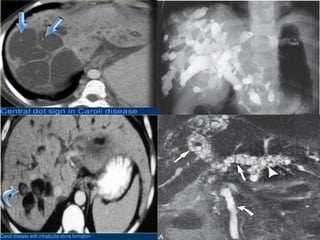

Caroli’s Disease

Caroli’s disease, also known as communicating cavernous ectasia, is

characterized by multifocal segmental saccular dilatation of the intrahepatic

bile ducts, a predisposition to biliary calculi and cholangitis, and an association

with various forms of cystic renal disease.

It is an autosomal recessive disease secondary to the ductal plate

malformation. It is associated with polycystic kidney disease, medullary

sponge kidney and medullary cystic disease.

Caroli’s disease usually manifests in adulthood; however, it can be seen in

newborns and infants.

Adult patients present with recurrent attacks of cholangitis and crampy right

upper quadrant pain with occasional fever and mild jaundice.

Infants and children may present with hematemesis caused by portal

hypertension from hepatic fibrosis.

Complications of Caroli’s disease include stone formation (95%) within

the dilated intra-hepatic ducts, recurrent cholangitis, and liver abscess.

There is also a 100-fold increase in incidence of bile duct carcinoma,

occurring in 7% of patients.

Caroli’s disease is best demonstrated by cholangiography which shows

saccular dilatations of the intrahepatic ducts, stones, strictures, and

communicating hepatic abscesses.

Ultrasound

May show dilated intrahepatic bile ducts (IHBD).

intraductal bridging: echogenic septa traversing the dilatedbile duct lumen.

smallportal venous branches partially/completely surroundedbydilatedbile

ducts.

intraductal calculi.

CT

multiple hypodense rounded areas which are inseperable from the

dilated intrahepatic bile ducts

“centraldot” sign: enhancing dots within the dilated intrahepatic bile duct

s, these intraluminal dots correspond to intraluminal portal veins

MRCP with three-dimensional display is an accurate method for

demonstrating Caroli’s disease because the luminal contents of the bile

ducts appear hyperintense in contrast to the portal vein, which usually

appears as signal void.

Cystic expansions of the intrahepatic biliary tract are depicted as oval-

shaped structures in continuity with the biliary tract.